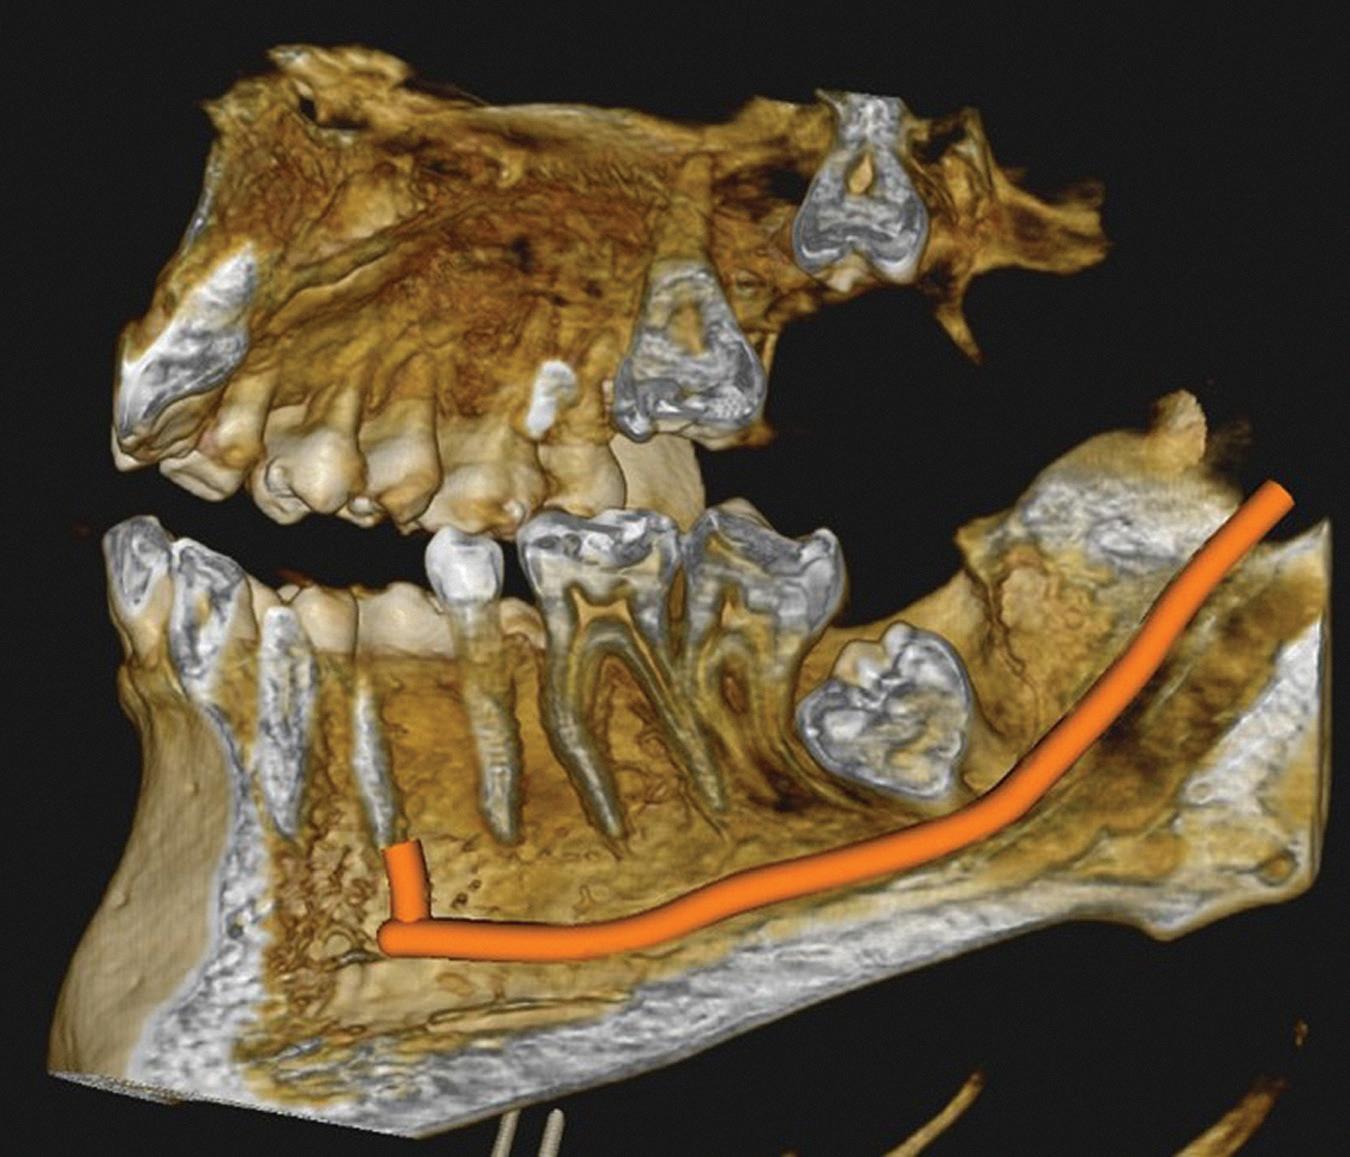

Figure 1: Radiographic Image of implants do not demonstrate bone loss due to the bisecting angle of the radiograph taken.

Figure 2: Radiographic image in a paralleling technique of implants dem onstrate moderate peri-implantitis with bone loss that will necessitate treatment.